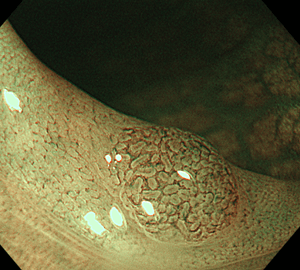

その病変のNBI観察像です。これを拡大して観察すると…

不整な表面構造と、血管の分布不均一・口径不同・蛇行を認めます。当院は、大腸がん検診(便潜血検査など)で異常が見つかった際の(陽性結果)、二次検診の精密検査としての大腸内視鏡検査(大腸カメラ/下部消化管内視鏡検査)にも対応しております。